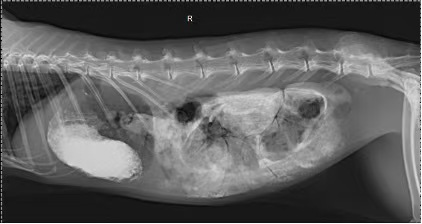

Today, we treated a 7-year-old rabbit whose owner brought it to the clinic after noticing that the rabbit was unwell. The rabbit had a poor appetite, reduced fecal output, and the feces were smaller than usual. What concerned the owner most was the rabbit